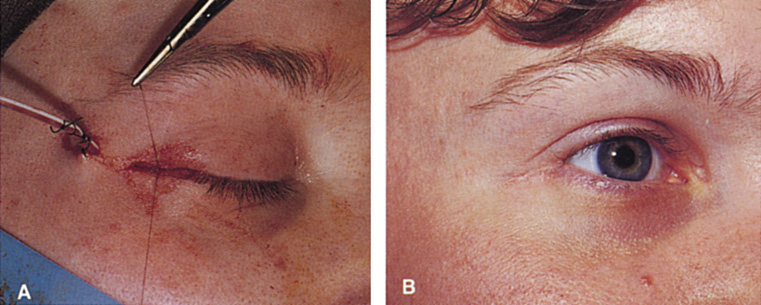

Fig. 12. A. The lateral canthotomy incision is reapproximated with simple closure

of the superior and inferior crura of the lateral canthal tendon. A drain

from the temporal fossa has been brought out through a separate stab

incision posteriorly. 12B. Excellent postoperative scar camouflage is obtained by this approach.

Fig. 12. A. The lateral canthotomy incision is reapproximated with simple closure

of the superior and inferior crura of the lateral canthal tendon. A drain

from the temporal fossa has been brought out through a separate stab

incision posteriorly. 12B. Excellent postoperative scar camouflage is obtained by this approach.